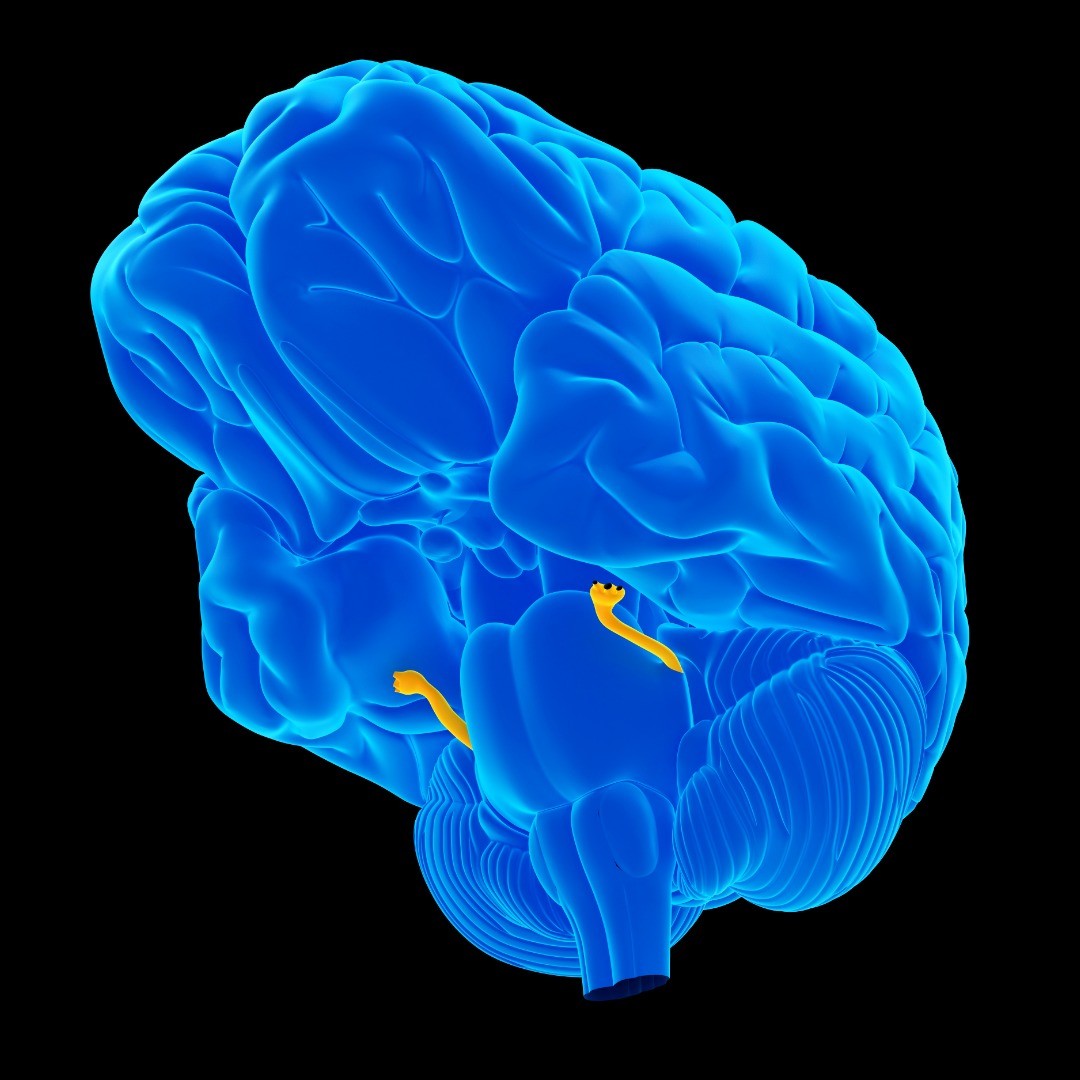

Microvascular decompression is brain surgery to remove pressure (decompression) caused by a very small blood vessel (microvascular) on a cranial nerve, usually the trigeminal nerve.

Microvascular Decompression is used to treat refractory (difficult to treat or unmanageable) facial pain or facial spasms caused by a compressed nerve:

Candidates for microvascular decompression surgery tend to be younger patients (under age 65) with glossopharyngeal neuralgia, hemifacial spasms or trigeminal neuralgia not caused by multiple sclerosis. Microvascular decompression may be an option if medications and other conservative care treatments have failed to provide relief.